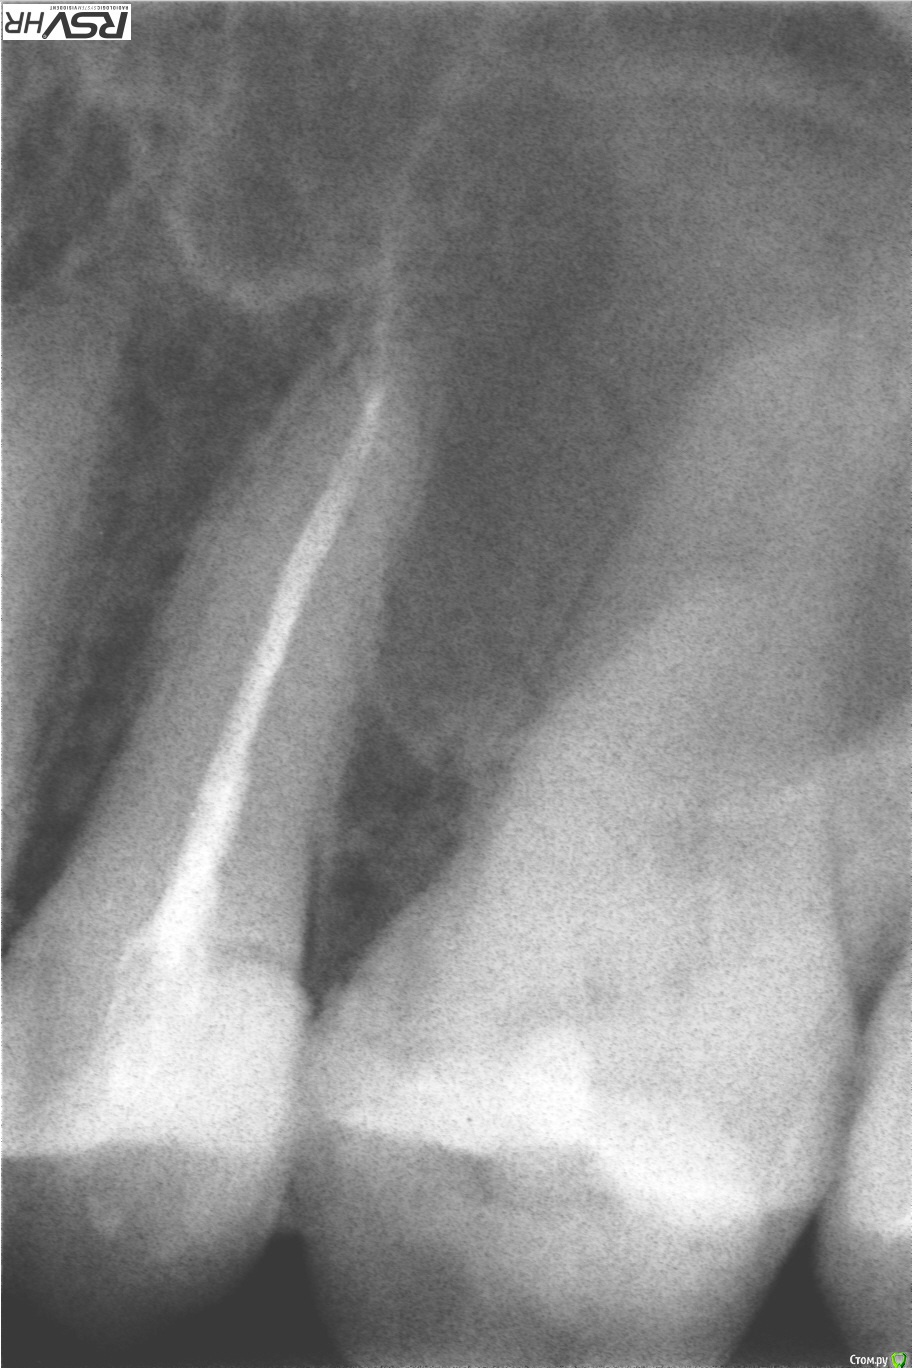

katrineigma Опубликовано 24 сентября, 2015 Поделиться Опубликовано 24 сентября, 2015 Была на приеме у стоматолога с пятым верхним зубом. Пришла вообще с другим, а этот и не беспокоил. Но сделали рентген и сказали надо удалять нерв. Потому что у этого зуба расширение периодонтальной щели, но пока не киста, как-то так, и если не пролечить сейчас, то потом вообще зуб придется удалять. Мне же зуб на снимке кажется абсолютно здоровым и теперь не дают покоя сомнения не зря ли мне удалили нерв. Прикрепляю рентген "До" и "После" лечения. Подскажите, действительно ли с зубом что-то не так? И заодно вопрос: канал запломбирован хорошо? Ссылка на комментарий

Romanson Опубликовано 24 сентября, 2015 Поделиться Опубликовано 24 сентября, 2015 Как давно ставили пломбу в этот зуб? Доктор, который депульпировал проводил какие-нибудь пробы для выявления живой нерв в зубе или нет (например, холодовую пробу)? После снятия старой пломбы доктор как-нибудь оценил состояние тканей под пломбой (был ли вторичный кариес под пломбой)? Слишком мало данных для того, чтобы делать какой-то вывод. Но, если интересно частное мнение, то если бы ко мне пришел пациент с таким зубом, и тесты на витальность оказались положительными (т.е. зуб реагировал как-нибудь на раздражители, например на холод, как здоровый зуб) я бы предложил за таким зубом понаблюдать (прийти через пол года, повторно сделать снимок и провести пробы). Канал запломбирован нормально. Ссылка на комментарий

katrineigma Опубликовано 24 сентября, 2015 Автор Поделиться Опубликовано 24 сентября, 2015 Как давно ставили пломбу в этот зуб? Доктор, который депульпировал проводил какие-нибудь пробы для выявления живой нерв в зубе или нет (например, холодовую пробу)? После снятия старой пломбы доктор как-нибудь оценил состояние тканей под пломбой (был ли вторичный кариес под пломбой)? Слишком мало данных для того, чтобы делать какой-то вывод. Но, если интересно частное мнение, то если бы ко мне пришел пациент с таким зубом, и тесты на витальность оказались положительными (т.е. зуб реагировал как-нибудь на раздражители, например на холод, как здоровый зуб) я бы предложил за таким зубом понаблюдать (прийти через пол года, повторно сделать снимок и провести пробы). Канал запломбирован нормально.Пломба, которая на первом снимке, была поставлена года 4 назад, а депульпировали зуб на днях. Проб никаких не проводили...После снятия пломбы уже не было комментариев, решение об удалении нервов было принято по рентгену еще до снятия пломбы, потому и возник вопрос, действительно по рентгену что-то видно, какие-то патологии? Ссылка на комментарий

katrineigma Опубликовано 25 сентября, 2015 Автор Поделиться Опубликовано 25 сентября, 2015 Не совсем понял. Вас беспокоил другой зуб, а патологию доктор нашел в этом? Так было? Если так, то определить, сделано ли все правильно, очень просто по отсутствию жалоб после лечения...Зуб беспокоил соседний, шестой, но тоже не болел, просто видно было, что там кариес и надо лечить, однако врач обратил внимание в первую очередь на пятый зуб, сказав, что он скорее всего мертвый, так как на нем очень большая пломба, послал на рентген пятого зуба, чтобы убедиться, что он всё-таки живой, и по рентгену же сказал, что надо удалять нервы. Сейчас вопрос даже не столько в том, правильно ли был запломбированы каналы, сколько в том, стоило ли их вообще пломбировать и убивать нервы пытаюсь понять действительно ли на рентгене что-то не так и что именно Ссылка на комментарий

katrineigma Опубликовано 27 сентября, 2015 Автор Поделиться Опубликовано 27 сентября, 2015 То есть только рентген? Никаких тестов в клинике не было вобще? Не стучали ничем по зубу тоже?Нет, ничем не стучали и тестов никаких не было...врач еще до рентгена сказал, что зуб скорее всего мертвый, на что я сказала, что он точно живой, врач удивился: "Такая огромная пломба и живой?", послали на рентген удостовериться,и, собственно вот....на рентгене, значит, все нормально и мои опасения, что зря нервы удалили, оправдались? Ссылка на комментарий

St. Опубликовано 27 сентября, 2015 Поделиться Опубликовано 27 сентября, 2015 Ну почти... По рентгену можно заподозрить проблему, не более. Окончательно сказать можно только после мероприятий описанных выше. Ссылка на комментарий